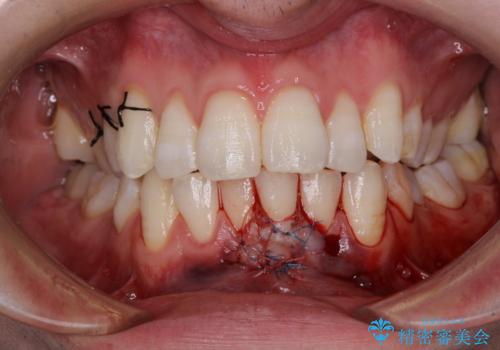

- 徐々に歯根が見えるようになり、気がついたら歯根のほぼ全てが見えるようなってしまったと言うことで来院された患者様です。

しみる症状はないものの、見た目が著しく悪く、汚れが溜まりやすいとのことで、歯肉移植による根面被覆を行うこととしました。

歯肉が非常に薄く、必要な被覆量が多いことから、1度の処置では十分な被覆は難しく、2度処置を行うことになる可能性が高いとお伝えしました。